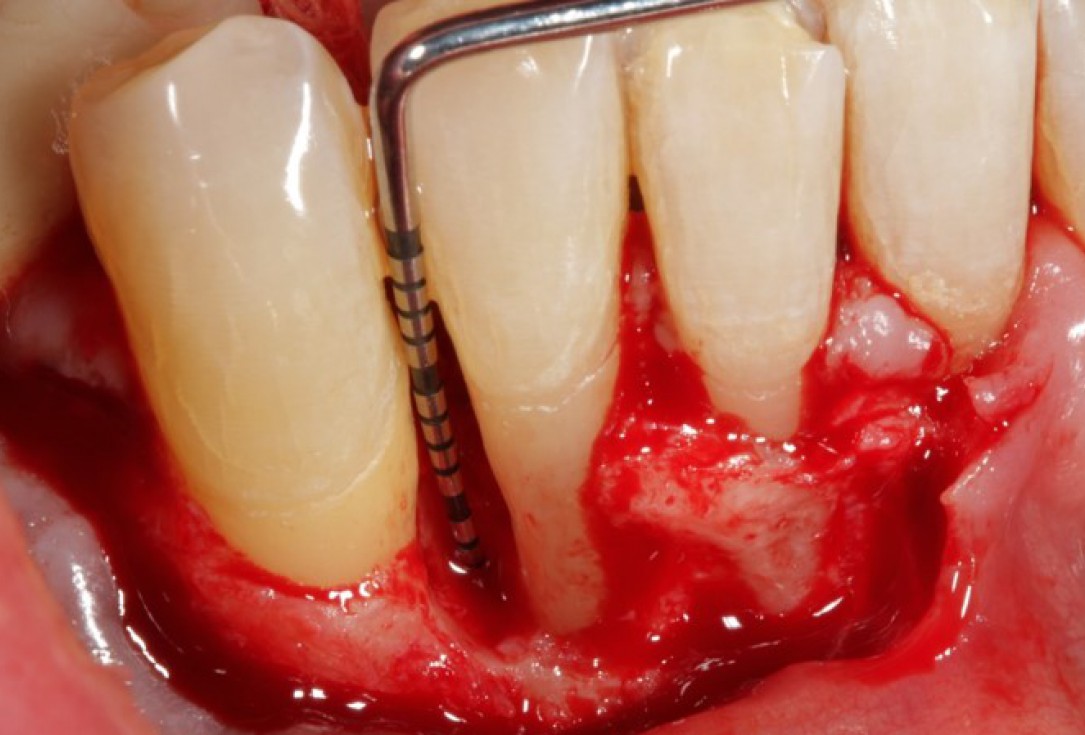

02/08 - Pre-surgical probing reveals a deep intrabony defect on the distal aspect of tooth 42.

Non-contained intrabony defect treated using Straumann® Emdogain® and a synthetic bone grafting material - Prof. Dr. Dr. A. Kasaj